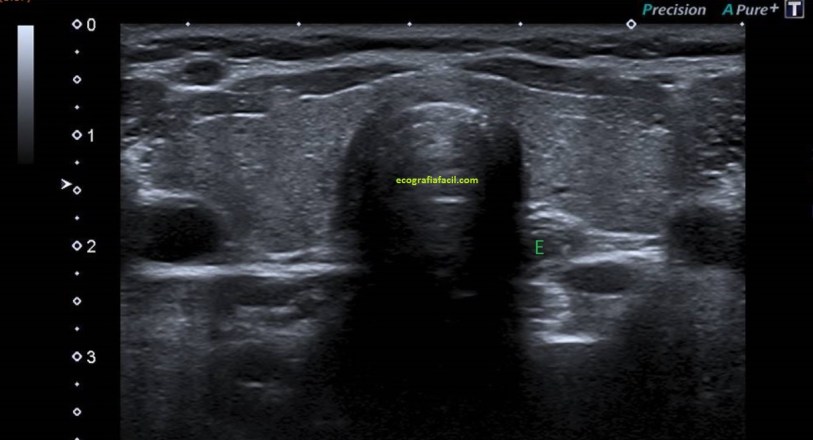

Se puede dar un vaso de agua al paciente y mirar el contenido del divertículo. Lo estudiamos en dos planos transversal y longitudinal. Eventualmente, lo mediremos.

La sonda está en transversal al lóbulo tiroideo izquierdo. Se visualiza el esófago (E) y divertículo de Killiam-Jamieson.

Se visualiza divertículo esofágico (killiam- Jamieson) en longitudinal en la imagen 5.

Lo que observamos es un divertículo esofágico en la pared anterior y lateral del esófago cervical. Divertículo de Killiam-Jamieson.